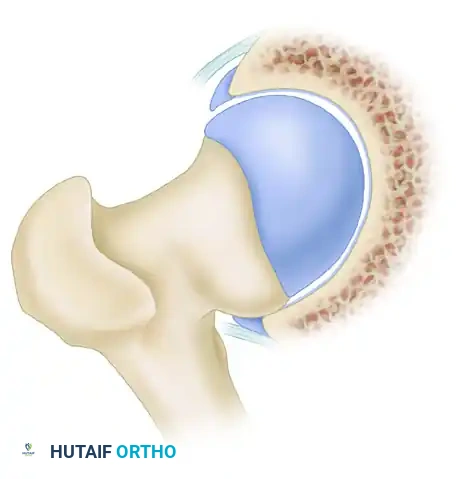

Cam impingement is predominantly observed in young, active male patients. It is characterized by an abnormally shaped, nonspherical femoral head with a decreased head-neck offset. This aspherical extension of the epiphysis (often referred to as a "pistol grip" deformity) creates a cam effect as the femoral head rotates into the acetabulum.

During dynamic hip flexion and internal rotation, the prominent cam lesion forcefully abuts the anterosuperior acetabular rim. Because the cam lesion is larger than the corresponding acetabular opening, it acts as a wedge, generating massive shear forces across the articular surface.

Over time, this repetitive shearing leads to delamination of the acetabular cartilage from the subchondral bone and subsequent avulsion or detachment of the labrum from the articular margin. The labrum itself is often pushed outward, resulting in an "outside-in" pattern of failure.